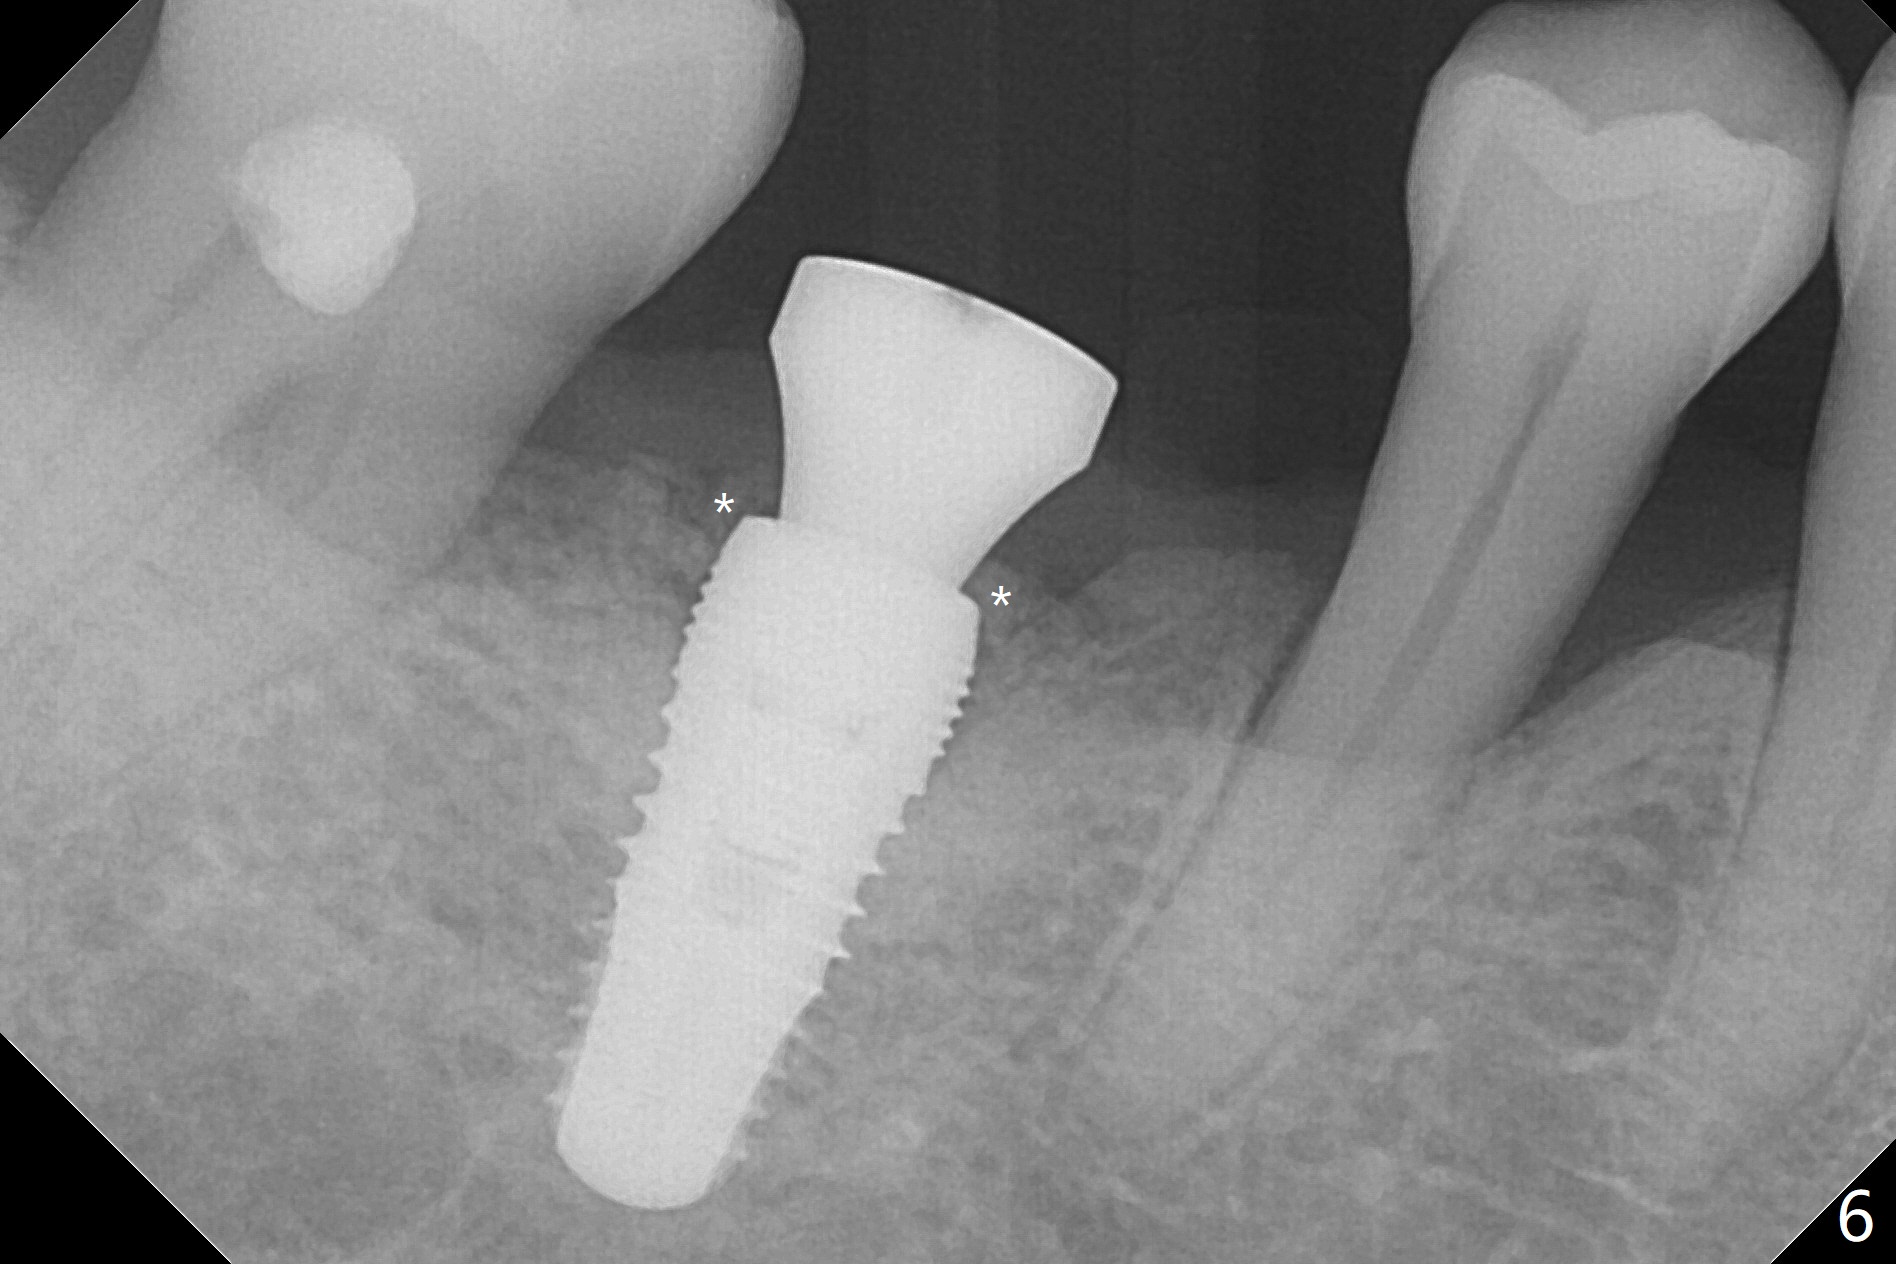

A 64-year-old man returns with history of a lump in the right submandibular region. Biopsy in a medical clinic shows inflammation. The implant crown at #30 has been cemented for ~ 4 years (Fig.1 (A: abutment)). The lingual plateau of the implant is exposed for 1-2 years asymptomatic (Fig.2 *). There is no deep lingual pocket when the crown and abutment are removed (Fig.3). Flap surgery confirms microthread exposure (circumferential, Fig.4). After removal of the microthreads with diamond bur (Fig.5), allograft (Fig.6 *), 6-month collagen membrane and a 6.5x5(3) mm healing abutment are placed. Following suturing, periodontal dressing is applied. The site remains asymptomatic 3 months postop, when an implant is placed subcrestal at #3.